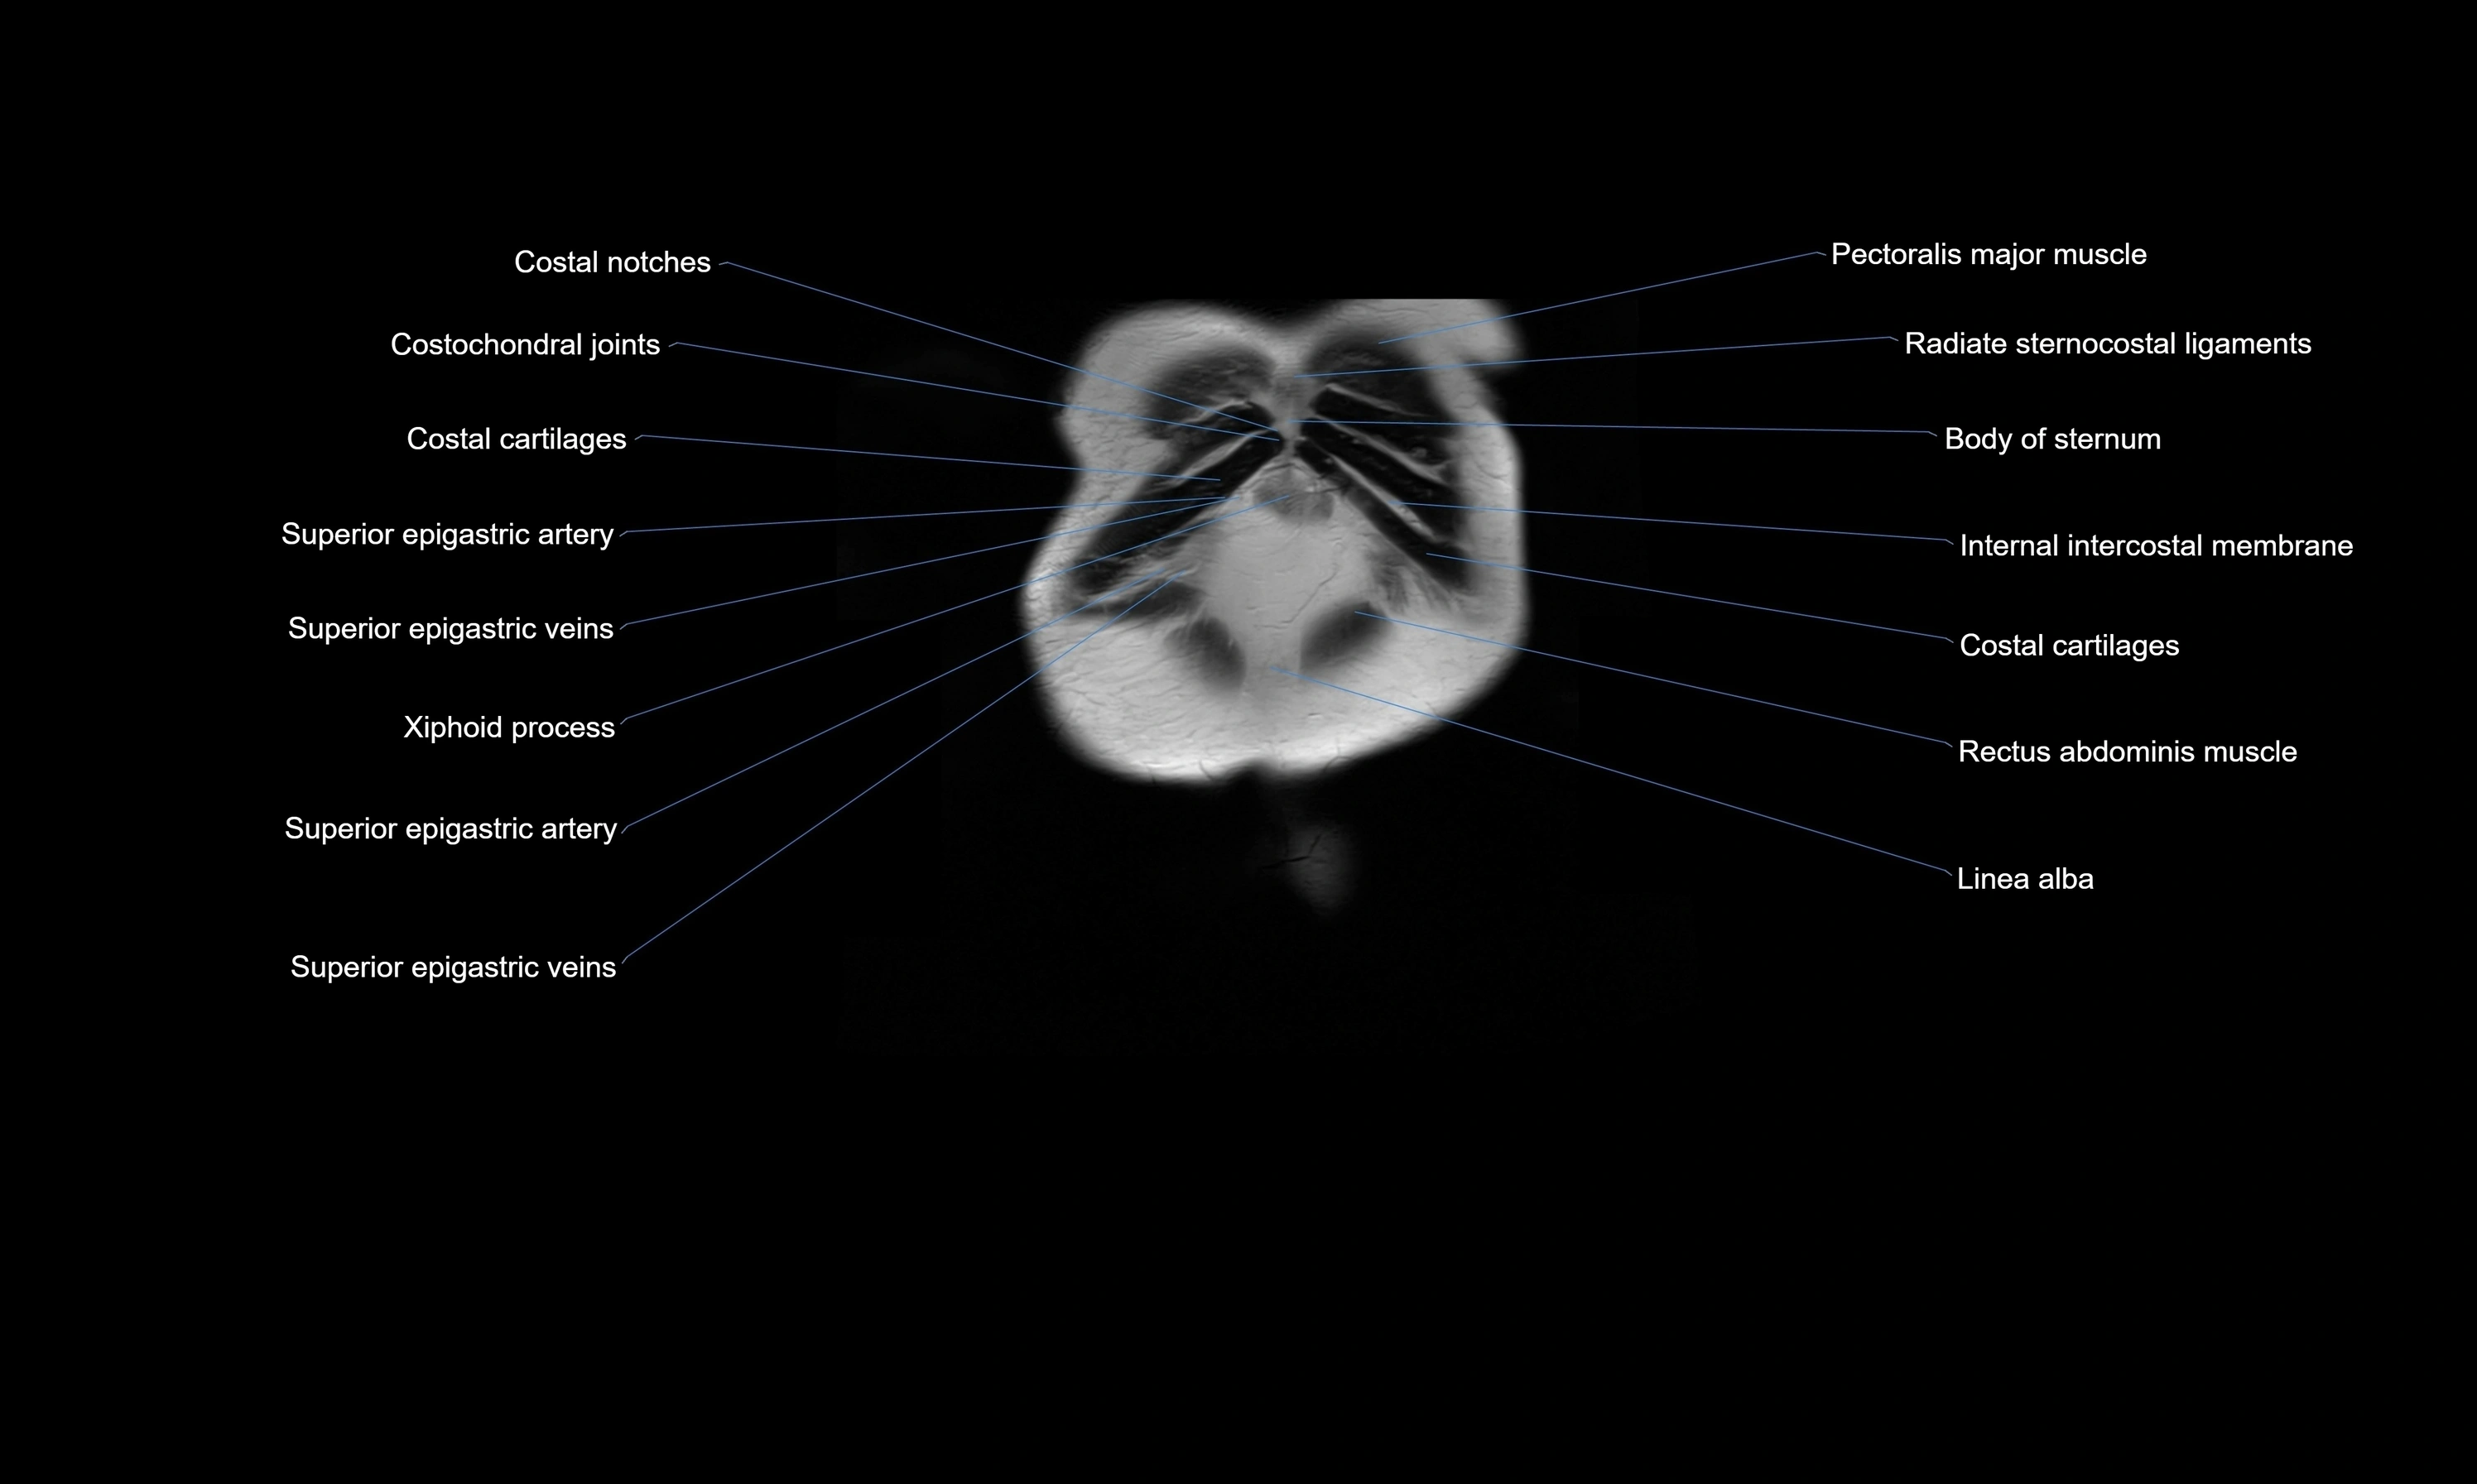

- Costochondral joints

- Internal thoracic artery

- Internal thoracic veins

- Linea alba

- Rectus abdominis muscle

- Superior epigastric artery

- Superior epigastric veins

- Transversus thoracis muscle